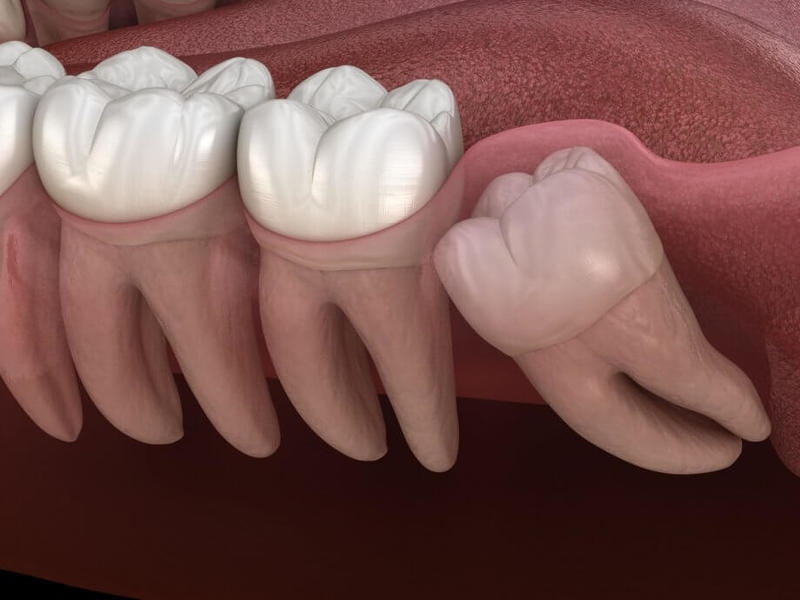

Răng mọc ngầm là răng mọc nằm sâu bên trong xương hàm hoặc ngay dưới nướu nhưng không thể tách nướu ra và trồi lên trên được. Những chiếc răng mọc ngầm hoàn toàn có thể mọc đầy đủ nguyên vẹn như những răng bình thường khác hoặc cũng có thể chỉ ở dạng nang.

Nguy cơ răng mọc ngầm có thể xảy ra ở mọi răng vĩnh viễn, trong đó hay gặp nhất là răng khôn. Bởi vì răng này thường mọc muộn nên thiếu khoảng trống cho răng trồi lên. Kế đến là các răng nanh hàm trên, răng hàm nhỏ của hàm dưới và răng cửa giữa của hàm trên cũng thường có răng mọc ngầm.